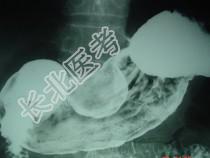

- 单项选择题男,52岁, 中上腹痛,影像检查如图, 最可能的诊断是  (    )

- A、慢性肥厚性胃炎

- B、胃癌

- C、胃溃疡

- D、胃平滑肌瘤

- E、胃平滑肌肉瘤